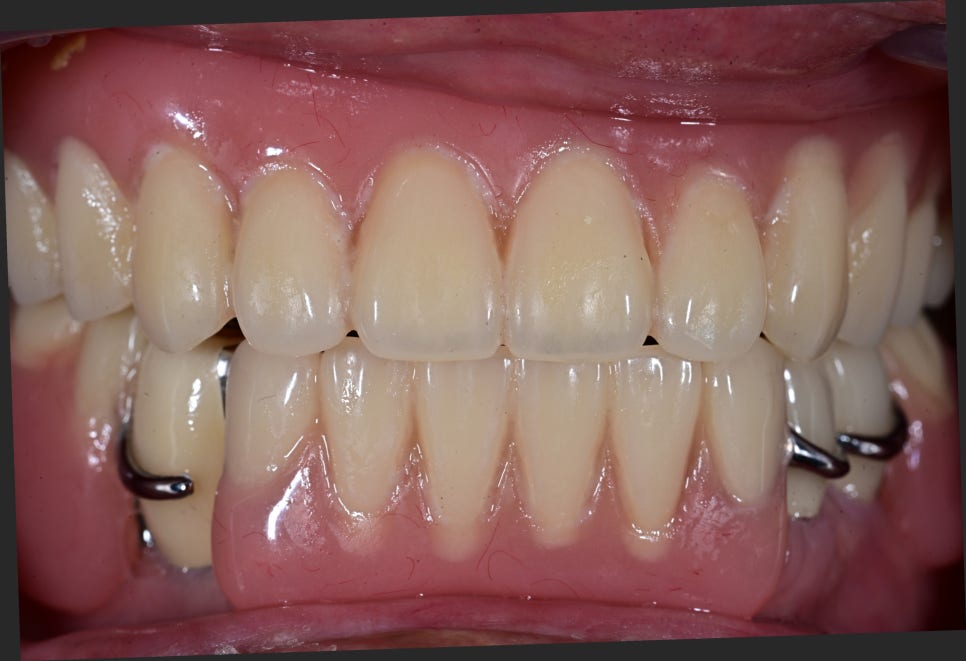

Comparison Before and After Treatment

※ The photos below are before-and-after comparison photos.

– Appearance after upper complete denture placement

– Appearance after lower implant placement and partial denture placement

<After>